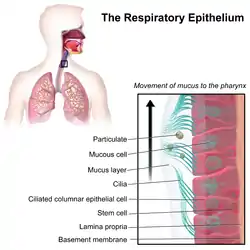

In the human respiratory system, mucus is part of the airway surface liquid (ASL), also known as epithelial lining fluid (ELF), that lines most of the respiratory tract. The airway surface liquid consists of a sol layer termed the periciliary liquid layer and an overlying gel layer termed the mucus layer. The periciliary liquid layer is so named as it surrounds the cilia and lies on top of the surface epithelium.[4][5][6] The periciliary liquid layer surrounding the cilia consists of a gel meshwork of cell-tethered mucins and polysaccharides.[7] The mucus blanket aids in the protection of the lungs by trapping foreign particles before they can enter them, in particular through the nose during normal breathing.[8]

Mucus is made up of a fluid component of around 95% water, the mucin secretions from the goblet cells, and the submucosal glands (2–3% glycoproteins), proteoglycans (0.1–0.5%), lipids (0.3–0.5%), proteins, and DNA.[7] The major mucins secreted – MUC5AC and MUC5B - are large polymers that give the mucus its rheologic or viscoelastic properties.[7][4] MUC5AC is the main gel-forming mucin secreted by goblet cells, in the form of threads and thin sheets. MUC5B is a polymeric protein secreted from submucosal glands and some goblet cells, and this is in the form of strands.[9][10]

In the airways—the trachea, bronchi, and bronchioles—the lining of mucus is produced by specialized airway epithelial cells called goblet cells, and submucosal glands. Small particles such as dust, particulate pollutants, and allergens, as well as infectious agents and bacteria are caught in the viscous nasal or airway mucus and prevented from entering the system. This process, together with the continual movement of the cilia on the respiratory epithelium toward the oropharynx (mucociliary clearance), helps prevent foreign objects from entering the lungs during breathing. This explains why coughing often occurs in those who smoke cigarettes. The body's natural reaction is to increase mucus production. In addition, mucus aids in moisturizing the inhaled air and prevents tissues such as the nasal and airway epithelia from drying out.[11]

Mucus is produced continuously in the respiratory tract. Mucociliary action carries it down from the nasal passages and up from the rest of the tract to the pharynx, with most of it being swallowed subconsciously. Sometimes in times of respiratory illness or inflammation, mucus can become thickened with cell debris, bacteria, and inflammatory cells. It is then known as phlegm which may be coughed up as sputum to clear the airway.[12][13]